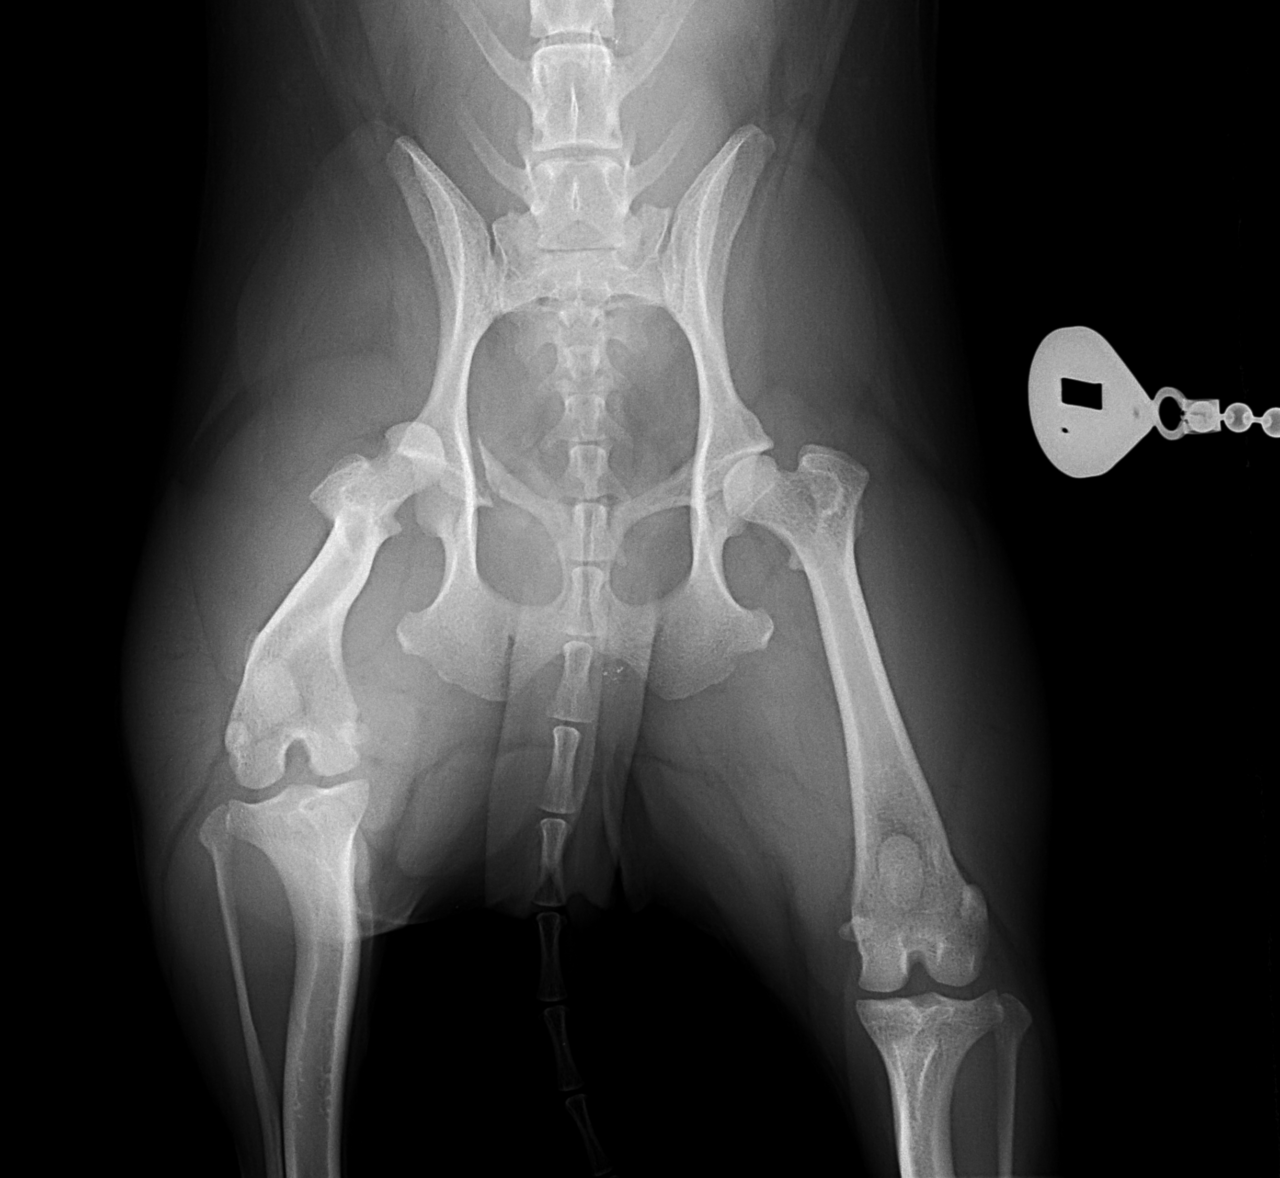

輪禍外傷による股関節脱臼の患者さんに対してBullet–Shaped Toggle Rod (BUSTOR)で整復を行いました。本症例は恥骨の骨折も併発していたため、CTで寛骨臼の評価も実施しました。低侵襲かつ短時間で整復が可能です。しばらくは安静が必要です。